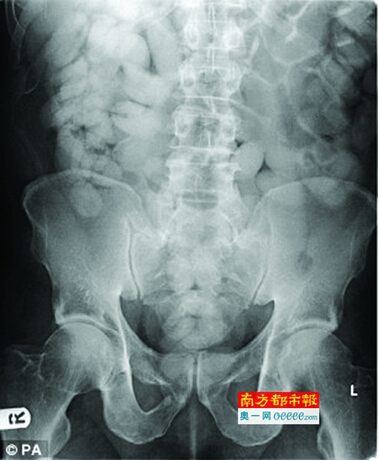

X光显示,一名运毒者的身体内被“塞进”多达120小包海洛因。

这是一幅令人窒息的图像:X光显示,试图过境的运输毒品者用身体做容器,把上百包海洛因“塞进”身体里。

在英国某处边境,一名外表看似正常的外籍人士在过关时被逮捕。特殊的X光设备显示,他的体内藏有含一类毒品的粉末多达120小包,价值数万英镑。